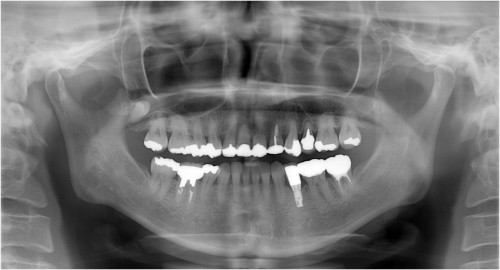

同パノラマ写真

術 前

インプラント埋入後→被せ物装着